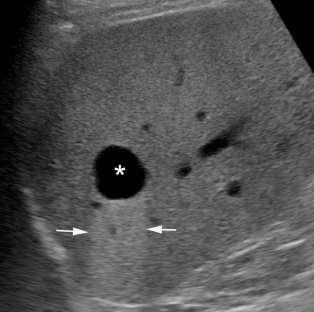

Echoszegény

Ezen a képen szintén a májat láthatjuk, melyen belül egy kifejezetten sötét kerekded eltérést azonosíthatunk (csillag). Ez a máj alapállományához képest hypoechogén megjelenésű. Mögötte a nyilakkal jelölt világosabb terület úgynevezett hangerősítés. Ez bizonyos esetekben segítheti a vizsgáló orvosnak a cisztát egyéb, echoszegény struktúráktól elkülöníteni.